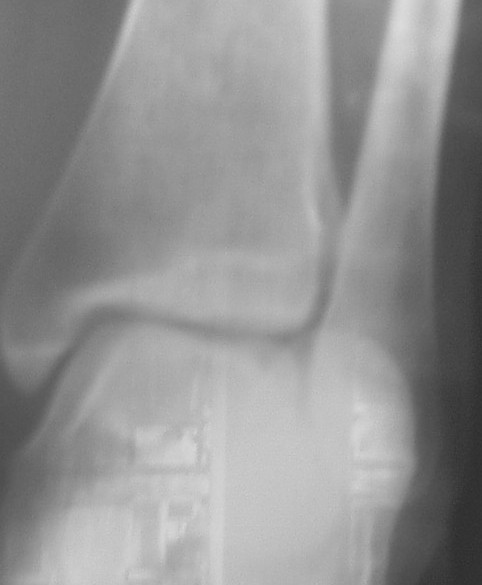

Прямой контрлатеральный сустав.JPG

На боковом довольно неплохой сустав, скудная информация о положении вилки сустава при косой рентгенограмме (Mortise view) из-за положения стопы во внутренней ротации и эквинуса во время ренгенограммы.